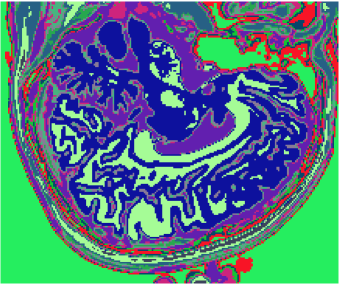

Figures 1 (band 0), 2 (band 1) and 3 (band 2) show PD- (proton density), - and -weighted MR images of the 97th slice, while figure 4 shows the R0-G1-B2 colored composition of the same slice.

Figures 5, 6, 7 and 8 show classification results, whilst figures 9, 10, 11 and 12 exhibit quantization results for the image of the 97th slice, figure 4, using methods KO, CM, KM and ODC, respectively. Image quantization is the procedure of constraining a determined image from its complete set of pixels to a smaller set of vectors with same dimensions feasible to represent the original image with a smaller gamute, according to a given fidelity measure. Herein this work we built quantization images just by changing the original pixels for the vectors of weights related to the classification results, i.e. the centroids of the unsupervised classification methods.